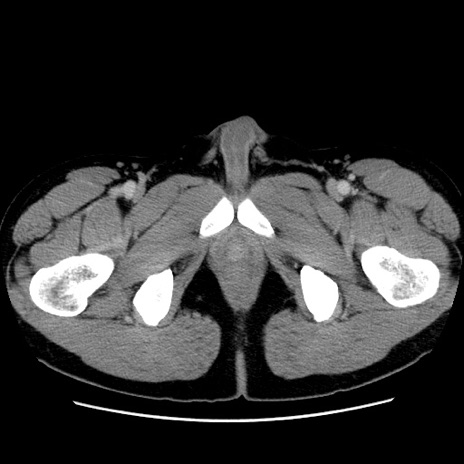

症例4(横断像)

【症例】30歳代男性

【主訴】腹痛、嘔吐

【現病歴】昨晩から突然の腹痛あり、その後嘔吐、軟便も出現。腹痛が改善しないため救急搬送となる。2日前にしめ鯖の食事歴あり。

【身体所見】意識清明、苦悶様、BP 135/90mmHg、BT 35.7℃、腹部:平坦、やや硬、心窩部〜臍部に自発痛、圧痛あり、筋性防御+、反跳痛-

【データ】WBC 8100、CRP 0.57